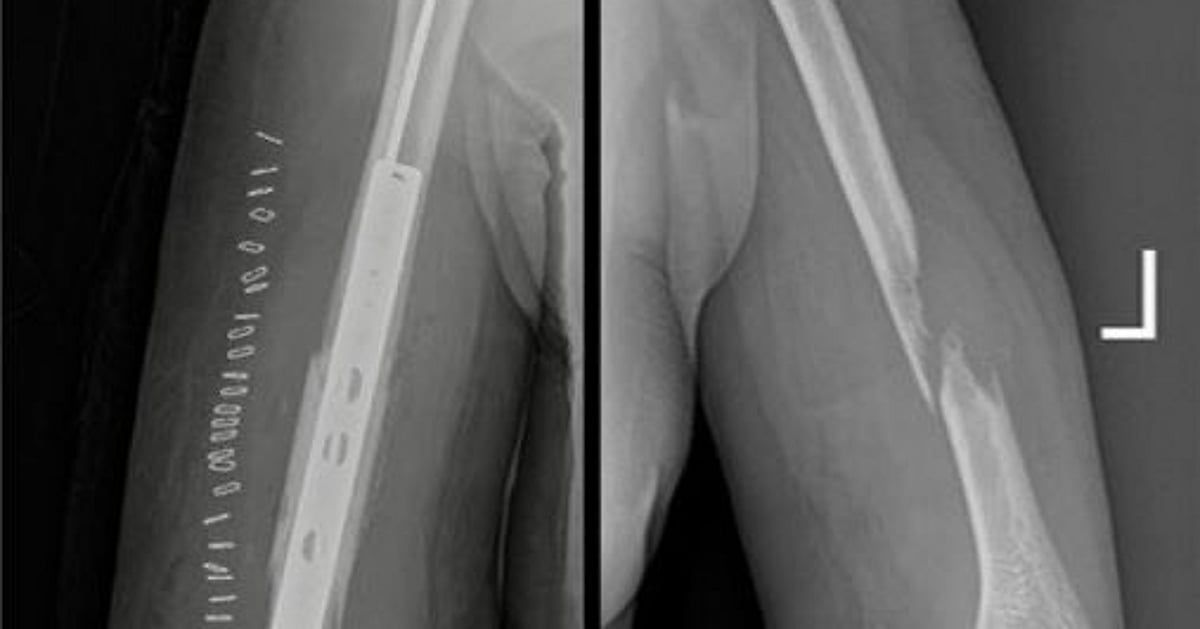

وتمكّن الفريق الطبي من استئصال الجزء المتآكل من العظم، وإعادة بناء الفراغ باستخدام إسمنت طبي ومتثبتات معدنية، مع الحفاظ التام على الأعصاب والشرايين الرئيسية دون أي ضرر.